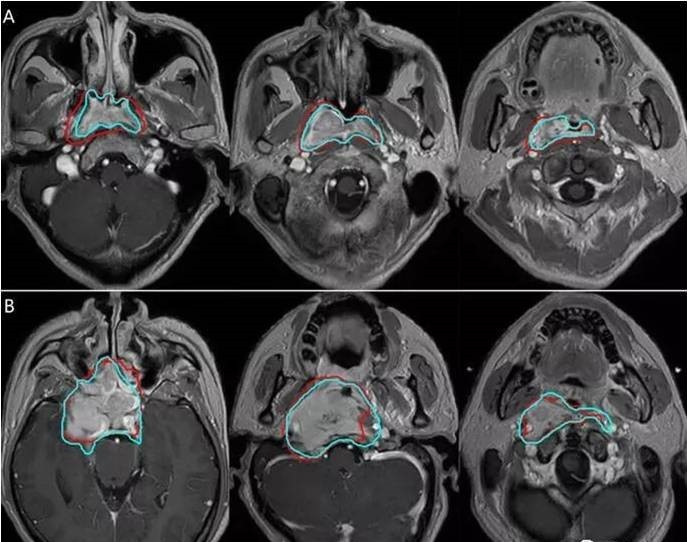

自治区南溪山医院放疗科引进了桂北地区首个人工智能(AI)靶区勾画平台,该平台能够快速、精准、高效地对头颈部、胸腹部肿瘤靶区进行自动勾画,有利于提高肿瘤靶区勾画的准确率,帮助医生制定更合理地治疗方案,“人工智能+专家审核”,有助于提高患者的生存期,减少放疗并发症,提高治疗后的生活质量。例如在鼻咽癌放疗过程中,加速器治疗机发出的射线要从不同的角度穿过肿瘤周围的脑干、脊髓、颞叶、眼球、视神经、耳蜗等40多个重要器官到达鼻咽部肿瘤区域,治疗精度要求在毫米级别,因此,鼻咽癌肿瘤靶区定位勾画的精确度就显得极其重要。因为照射不足可能导致肿瘤复发,照射过度会增加放射性脑坏死、听力下降、视力下降、言语含糊等严重的后遗症。但如今,鼻咽肿瘤靶区的勾画却普遍为人工勾画,准确性基本依赖于放疗科医生的经验,存在不快(3-10小时)、不准(准确率<70%)、不狠(变异超过50%)的问题。

作为放射肿瘤治疗流程中不可或缺的重要组成部分,软件运用先进的配准算法提供了自动勾画、自适应放疗、融合配准、剂量叠加等一整套完整肿瘤学工具,同时具备独有的QA工具和多项专利工具。在提高配准及勾画精确度、节省时间成本等多方面协助科室成功实施CT 与多序列核磁共振影像、PET-CT影像的多模态融合配准等多项临床工作。